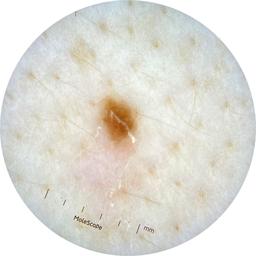

ISIC_0301375

1986 x 1986

acquisition_day 331

age_approx 35

anatom_site_1 Trunk

anatom_site_2 Anterior trunk

anatom_site_general anterior torso

diagnosis_1 Benign

diagnosis_confirm_type single image expert consensus

image_type dermoscopic